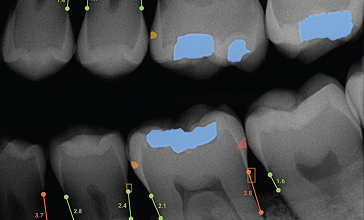

The field of dentistry has experienced remarkable transformations over the past few decades, largely due to technological advancements. Among the most revolutionary changes is the integration of digital technology into dental practices, known as digital dentistry. This shift has significantly enhanced diagnostic accuracy, treatment efficiency, patient comfort, and overall outcomes. From digital impressions to 3D printing, artificial intelligence (AI), and computer-aided design and manufacturing (CAD/CAM), digital dentistry has redefined the way dental care is delivered.

Digital dentistry refers to the use of digital technologies and devices to perform dental procedures. It encompasses any dental technology or device that uses digital or computer-based components, rather than mechanical or manual techniques. The scope of digital dentistry is vast and continues to expand as innovation grows.